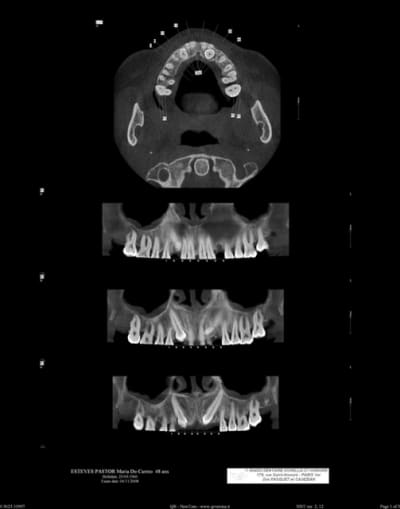

voir scan ci-joint

je dois extraire les deux canines incluses car la patiente a perdu ses lactéales.

je vais les extraire car j'ai décidé de poser deux implants

maintenant faut pas oulier que extraire les canines peut être extrêment délabrant et que poser des implants derrière c'est pas forcément une évidence. Pense aussi que les incisives sont en rapport étroites avec les canines et que tu peux les léser au passage.

Le problème c'est les extraire en conservant l'os autour mais vu les morceaux c'est pas gagner, en espérant qu'il n'y pas de plages d'ankylose.

je vais regarder tes scan plus précisement et si j'ai une idée ...